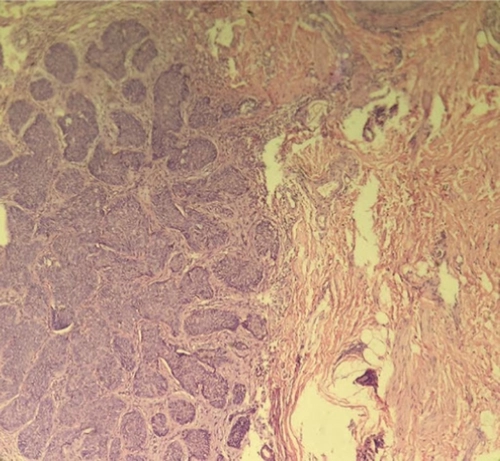

برای تأیید تشخیص، بیوپسی برشی (incisional biopsy) از ضایعه انجام شد. پاتولوژی ضایعه نشان داد:

تکثیر نئوپلاستیک درم از سلولهای اپیتلیال کوچک

نسبت بالای هسته به سیتوپلاسم

تشکیل دستههای نامنظم با پالیسادینگ سلولها در محیط (شکل ۲)

شکل ۲ — مقطع بافتشناسی نشاندهنده تکثیر نئوپلاستیک سلولهای اپیتلیال کوچک با نسبت هسته به سیتوپلاسم بالا و پالیسادینگ محیطی، به نفع BCC